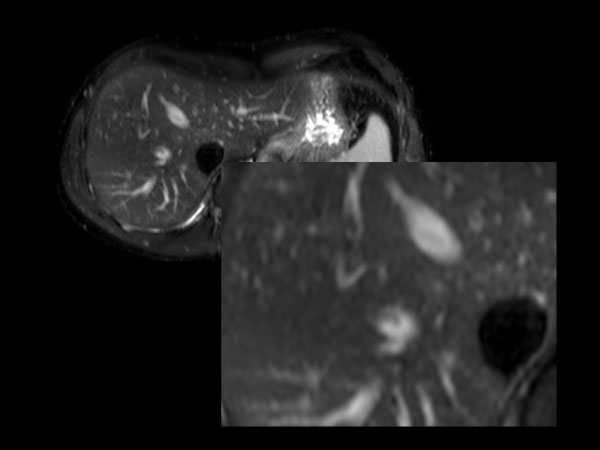

62 year old patient with huge, non-cirrhotic liver tumor. Question is if the portal vein is closed or not which has a direct influence on treatment options. Portal vein turned out to be open and patient was referred for embolization. No other tumors / lesions were found.

Axial  dynamic mDIXON (post-gado)